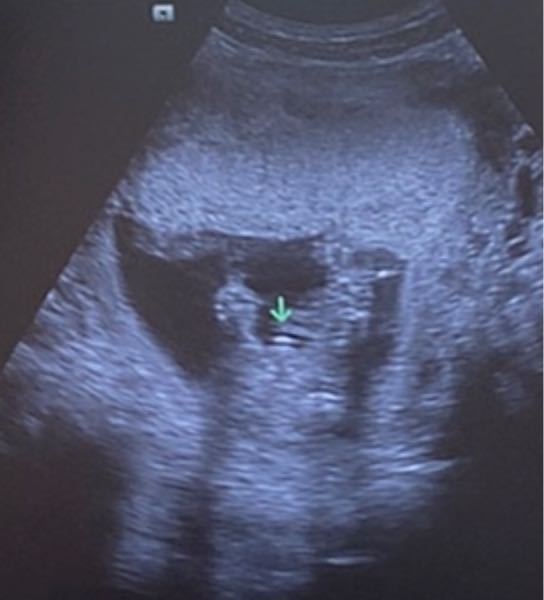

でも実は、赤ちゃんの性別は精子が卵子に受精した瞬間には決まっているのです。 精子に性別決定権がある 人間の体は細胞内にある2本1対の染色体によって構成されていて、男女に共通する22種類の 「常染色体」 44本と、性を決定する 「性染色体」 2本の46本からなっています。21/8/14 突起物が上向き→男児角度が30度ほど突起物が平行or下向き→女児角度が10度ほどらしく11週→60 Beautiful 4dエコー 女の子 突起物 Sumaho 妊娠13週に入ると子宮の大きさは小さなメロンほどになり早い人だと胎動を感じることが出来ます 12週を超えると流産のリスクもぐっと下がるので安4/6/17 ピーナッツのような 突起物 を確認することができます。 エコー写真や動画で突起物が確認できたら 高い確率で男の子 だと診断できます。 女の子 の場合は、突起物はなく、 太ももの間に 木の葉のようなもの が見えます。 また、子宮と膀胱がふたつの黒い点として

10/5/18 妊娠6ヶ月・22週目でも分からなかった赤ちゃんの性別 6ヶ月検診はじっくりとエコーでチェックが入りました お股の間に突起物が見えるような見えないような お腹の膨らみ方や表情などで性別を予測する人も お腹の出方で性別を判断する人 お母女の子 エコー 写真 突起物 エコー検査で、赤ちゃんの性別が判明するのはいつごろなのでしょうか。写真の見分け方や男の子、女の子それぞれの見え方の特徴を画像付きで解説します。男の子はピーナツ状の突起物、女の子は木の葉やコーヒー豆が股間に見えますが、ときには判定間違いも 妊娠 こんにちわ。28歳の妊婦です。 現在16週4日で、赤ちゃんの性別のことがとても気になっています。私はずっと前から女の子が希望で、主人はどちらかというと男の子がいいかな?というかんじです。悪阻